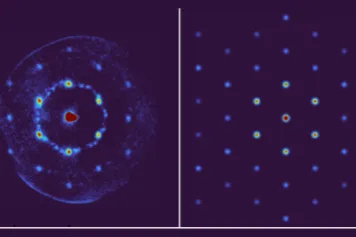

Grâce à un modèle murin, une nouvelle étude éclaire le rôle central du striatum, une région clé du cerveau, dans la prise de décision soit la sélection des actions en fonction des résultats attendus. Elle a été dirigée par Alban de Kerchove d'Exaerde, Directeur de recherches FNRS au Neurophy lab de l'ULB et investigateur du WEL Research Institute, et menée en collaboration avec l’Institut de Génomique Fonctionnelle (IGF) de Montpellier.

Le striatum est fortement impliqué dans les comportements moteurs, cognitifs et émotionnels. L'étude a mis en évidence trois types de profils cognitifs :

Les découvertes qui ont été faites dans le cadre de cette étude offrent un éclairage précieux sur les mécanismes cérébraux qui sous-tendent nos décisions au quotidien. Elles fournissent également des informations sur la manière dont différentes substances, telles que la caféine et la cocaïne, peuvent affecter les individus en fonction de leurs traits de caractère en matière de prise de décision. Ces recherches ouvrent aussi la voie à de nouvelles pistes thérapeutiques pour les troubles du comportement, comme les addictions ou les troubles du contrôle de l’impulsivité.